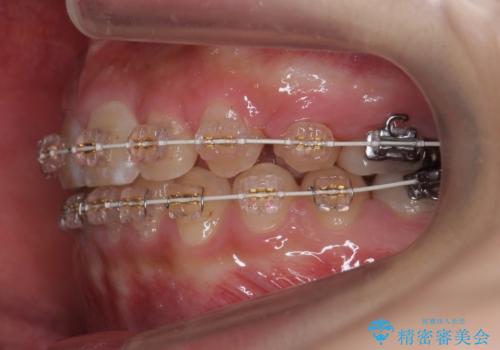

- 審美装置

- 3年2ヶ月

- 上の小臼歯を2本抜歯して矯正を行いました。

一般的には、抜歯を行うと前歯はより内側に倒れこむため、初めから内側に倒れ込んでいると矯正の難易度は上がります。

今回は上の前歯が内側に傾いている症状があり(Angle Ⅱ級2類)、その修正に時間がかかっています。

奥歯のかみ合わせが、歯と歯が向かい合わせになっておりまた、歯ぎしりも多い方で装置の脱離も頻繁にありました。

ワイヤー矯正ではやや難しい症例でした。